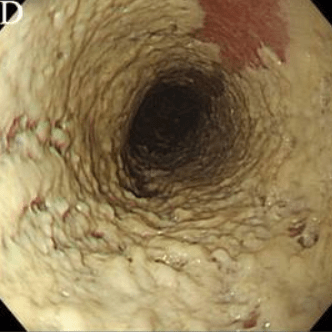

Эндоскопическая классификация кандидозного эзофагита по Kodsi

Степень I: Несколько приподнятых белесоватых бляшек размерами до 2 мм в диаметре, с гиперемией, но без отека или язв.